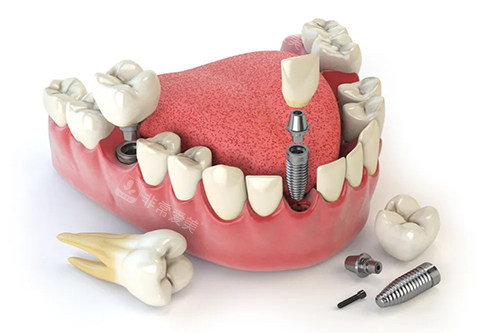

牙齿种植牙模型卡通示意图

牙齿种植牙模型